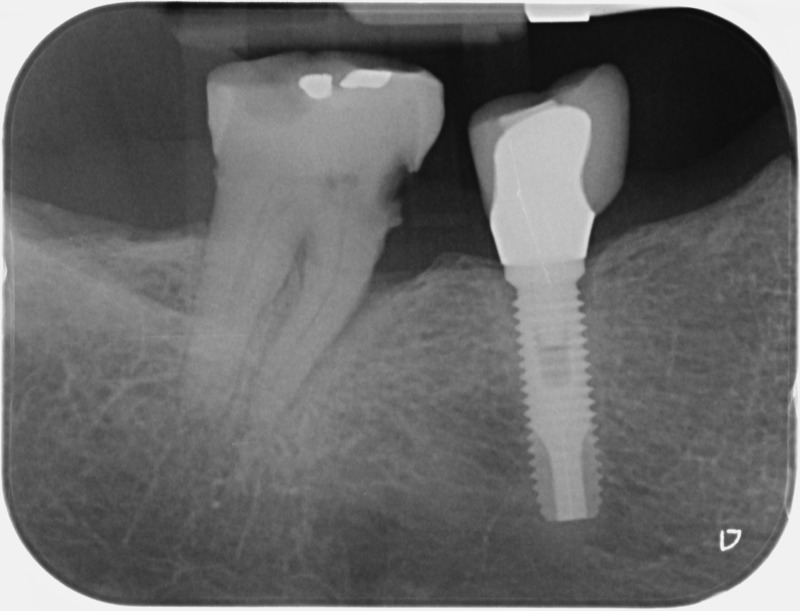

• Couronnes sur implants : Lorsqu’un implant est posé en remplacement des racines d’une dent, il est conçu pour recevoir d’abord un pilier vissé puis une couronne céramique. Le couple couronne - implant se substitue à la dent manquante pour en assurer les mêmes fonctions. Nous pouvons également adapter un bridge sur plusieurs implants dans le cas d’un édentement plus important.

Avant